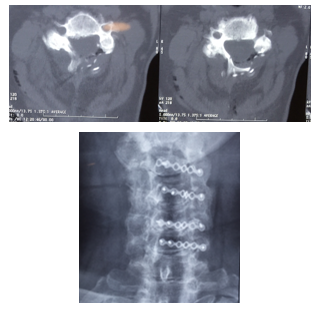

Con respecto a la imagenología se comparó balance sagital en la Rx preoperatoria y al año o más. Se clasifico en: lordosis, recta, cifotica o sigmoidea. En todos los casos se valoró la presencia de alteración de señal medular en la RNM de manera preparatoria y como control en la evolución.

En la Figura 4 vemos el esquema de la técnica original, empleada por nosotros, Mostramos la imagenología de uno de nuestros casos clínicos con una canal estrecho cervical destacado en la RMN de la Figura 5, y la Rx posoperatorio en la Figura 6.

42 pacientes se constató alteración de señal medular en la RNM preoperatoria. En 12 casos se observó cambio alteración de balance sagital al año. Antes del año de iniciados los síntomas fueron intervenidos 54 pacientes.

De los pacientes que presentaron alteración en el balance sagital. Doce (30%) pasaron lordosis a recta, 4 de recta a cifotica. No encontramos diferencias en la evolución clínica de estos con respecto a los que no presentaron cambios en rx de perfil. Esto debería explicar el porqué de la indicación relativa del open door en paciente con cifosis cervicales. Dado que existe una tendencia luego de la cirugía a la cifotización del segmento.

Limitaciones del estudio: no contamos con Rx funcionales pre operatorio ni post operatorio. Actualmente en el servicio las solicitamos de forma rutinaria. No Contamos con resonancia magnética y tomografía post operatoria por lo que no podemos obtener conclusiones en cuanto a la evolución imagenológica.